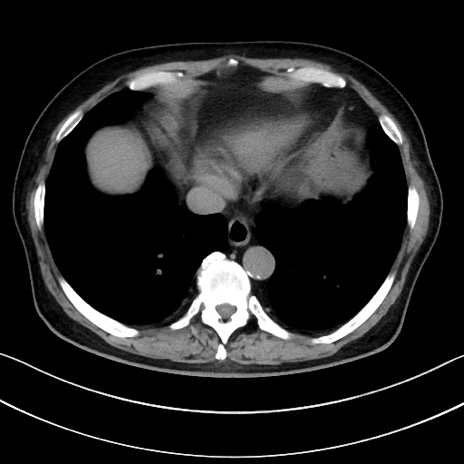

冠状断像

【症例】70歳代男性

【主訴】腹痛

【現病歴】今朝から腹痛あり。全体的に痛い。特に左上の方。排ガスが今日はない。冷や汗が出る。

【既往歴】直腸癌術後

【身体所見】左側腹部〜上腹部に圧痛あり。腹膜刺激症状明らかなではない。軽度反跳痛。左下腹部に術後瘢痕あり。

【データ】WBC 7700、CRP 0.02